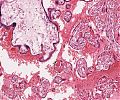

• A45 Placentopathia diabetica

Plumpe, unreife Plazentazotten, intervillöses Fibrin.

Persistenz embryonaler Zotten